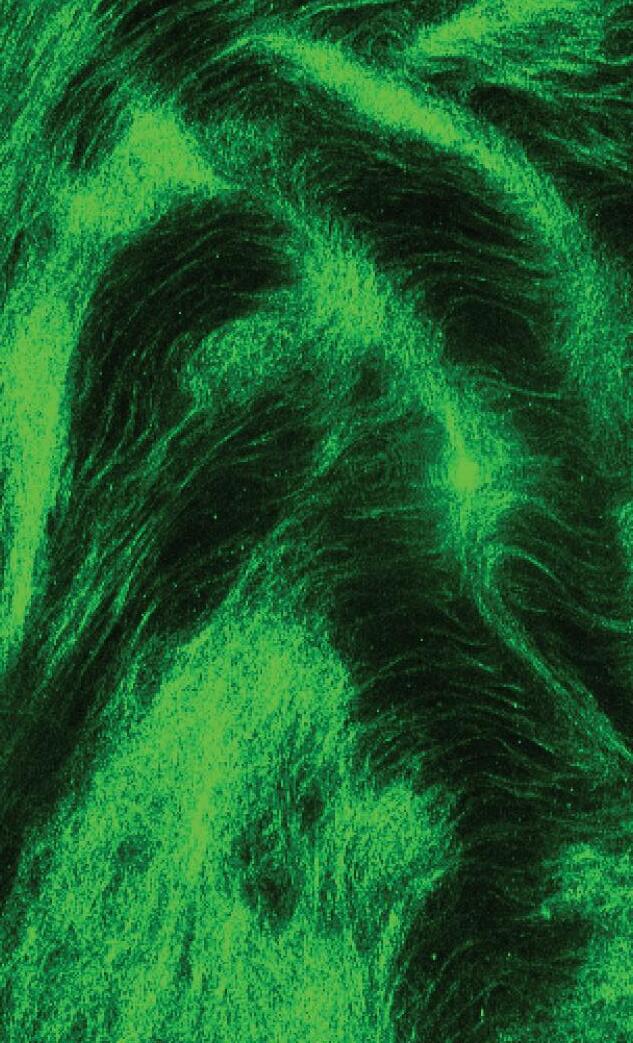

An image of human vitreous, shown after dissection and incubation in saline, from the laboratory of Eileen Hwang, MD, PhD.

Eileen S. Hwang, MD, PhD

$951,220 through 2028

“Cellular, Molecular and Physical Mechanisms of Vitreous Structural Heterogeneity Underlying Posterior Vitreous Detachment”

Hwang will study age-related changes in the vitreous, or gel that fills the eye, which can cause blinding retinal detachments. Understanding this process could help identify a way to prevent retinal detachments in high-risk patients.